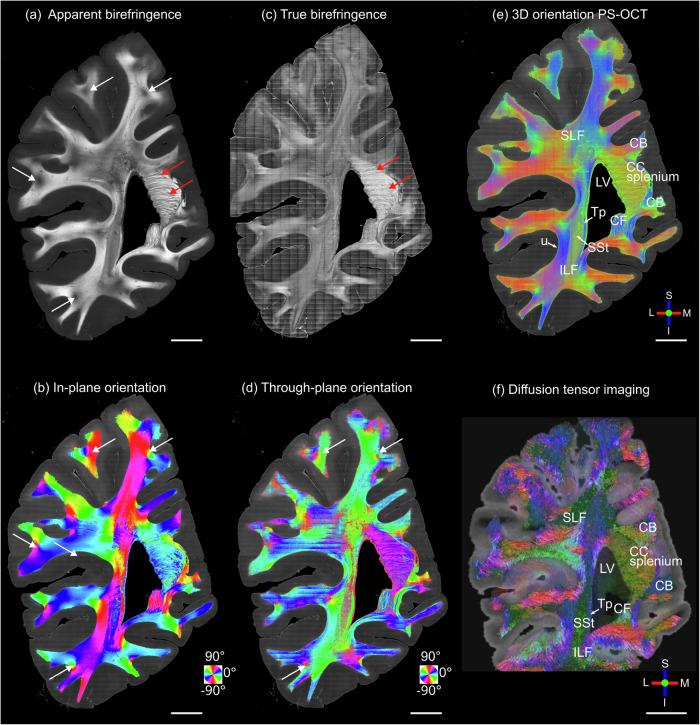

The accurate measurement of three-dimensional (3D) fiber orientation in the brain is crucial for reconstructing fiber pathways and studying their involvement in neurological diseases. Comprehensive reconstruction of axonal tracts and small fascicles requires high-resolution technology beyond the ability of current in vivo imaging (e.g., diffusion magnetic resonance imaging). Optical imaging methods such as polarization-sensitive optical coherence tomography (PS-OCT) can quantify fiber orientation at micrometer resolution but have been limited to two-dimensional in-plane orientation, preventing the comprehensive study of connectivity in 3D. In this work we present a novel method to quantify volumetric 3D orientation in full angular space with PS-OCT in postmortem human brain tissues. We measure the polarization contrasts of the brain sample from two illumination angles of 0 and 15° and apply a computational method that yields the 3D optic axis orientation and true birefringence. We further present 3D fiber orientation maps of entire coronal cerebrum sections and brainstem with 10 μm in-plane resolution, revealing unprecedented details of fiber configurations. We envision that our method will open a promising avenue towards large-scale 3D fiber axis mapping in the human brain as well as other complex fibrous tissues at microscopic level.

准确测量大脑中的三维(3D)纤维方向对于重建纤维通路以及研究它们在神经疾病中的作用至关重要。轴突束和小束的全面重建需要高分辨率技术,这超出了当前活体成像(例如,扩散磁共振成像)的能力。诸如偏振敏感光学相干断层扫描(PS-OCT)之类的光学成像方法可以在微米分辨率下量化纤维方向,但仅限于二维平面内方向,从而阻碍了对三维连通性的全面研究。在这项工作中,我们提出了一种新颖的方法,可利用PS-OCT在死后人类脑组织中在全角度空间中量化体积3D方向。我们从0°和15°的两个照明角度测量大脑样本的偏振对比度,并应用一种计算方法来得出3D光轴方向和真实双折射。我们进一步展示了整个冠状大脑切片和脑干的3D纤维方向图,其平面分辨率为10μm,揭示了纤维结构前所未有的细节。我们设想,我们的方法将为在微观层面上对人类大脑以及其他复杂纤维组织进行大规模3D纤维轴映射开辟一条充满希望的途径。